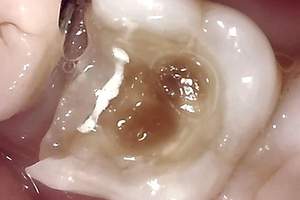

神経に達した深い虫歯

皆さんに質問になります。写真を見て、この虫歯を治療する際は、痛みがありそうですか?それとも、痛みがなさそうですか?

はい、答えは「痛みがありそう」です。

皆さん、虫歯が進行して歯の神経に達するような場合、虫歯治療で痛みが出る可能性があります。もちろん、麻酔をしっかりと行いますが、それでも痛みや炎症が強い場合は、phの関係で麻酔が効きにくいです。

神経まで達した深い虫歯を表した口腔内のイメージ画像